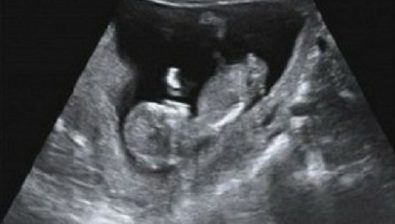

Ultrasound at 11 Weeks

Like mentioned before, the head makes up about half of your baby’s entire length. It is starting to uncurl from the body more than before. As the neck develops and gets longer, the chin seems to lift up from the chest.

One especially sweet formation is that fingernails now appear on your baby’s hands. Toenails will soon follow.

Although you might not know your baby’s gender for a while longer, he/she is slowly transforming into one gender or the other.

External male or female genitalia is more distinguished and will continue to develop in the coming months.